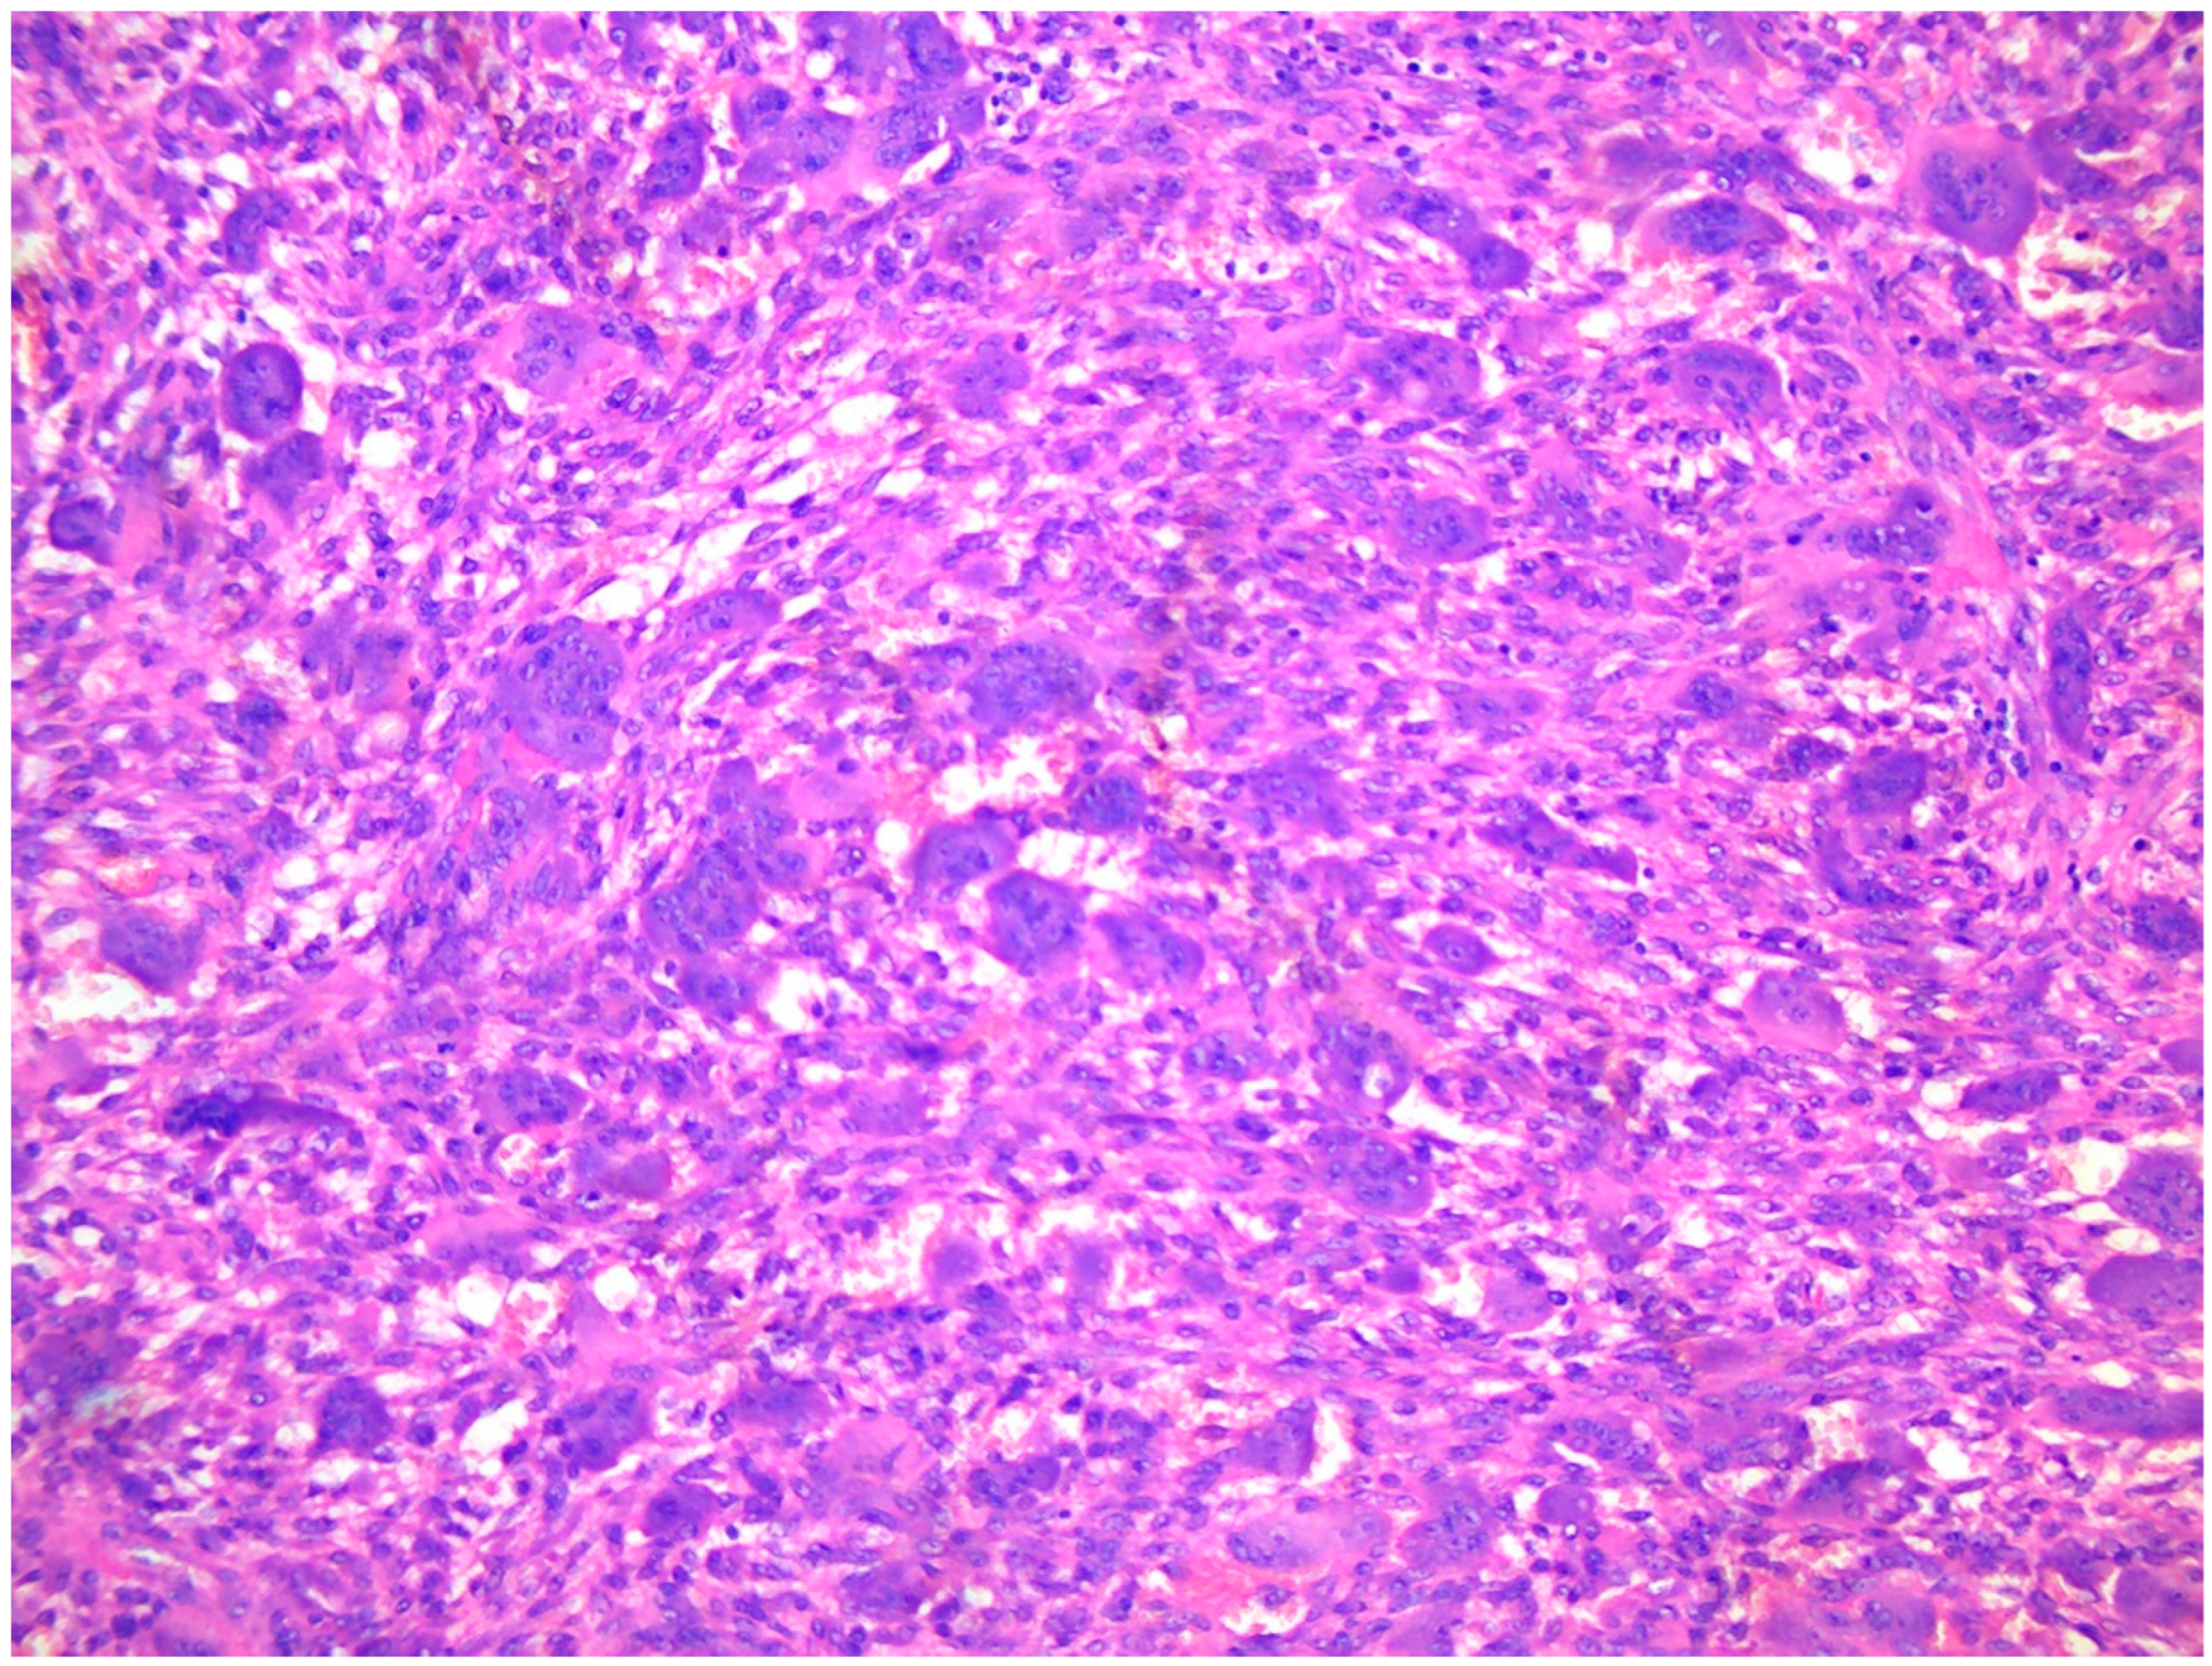

4.2. Tissue Biopsy